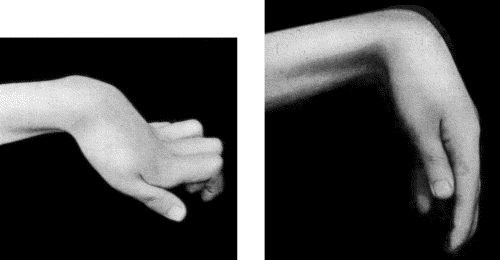

359 90.Drop-Wrist following Fracture of Shaft of Humerus

365 91.To illustrate the Loss of Sensation produced by Division of the Median Nerve

367 92.To illustrate Loss of Sensation produced by Complete Division of Ulnar Nerve